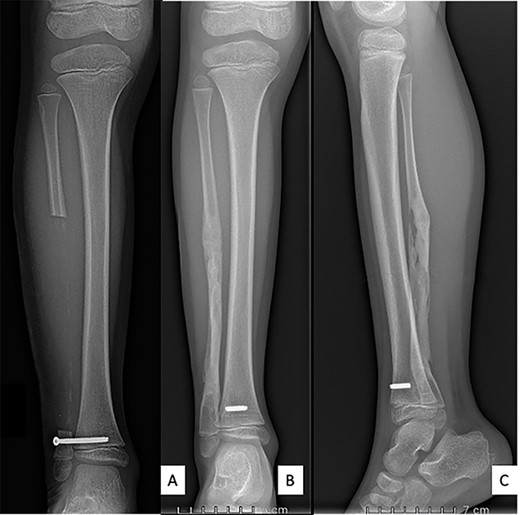

The initial diagnosis hypothesis was chronic osteomyelitis due to the history of periodontitis. A 14-cm fibulectomy was performed through a posterolateral approach (Figs 3 and 4) with periosteum preservation. A percutaneous cannulated screw was placed in the tibiofibular syndesmosis to prevent ascension of the lateral malleolus.

Anteroposterior radiograph and lateral view after right fibulectomy. (A): at 2-postoperative-weeks: preservation of the periosteum allowed progressive formation of new bone. (B) and (C): at 1-postoperative-year: a new fibula is reappeared. The syndesmosis screw broke with weight-bearing and only the fibular part of the screw was removed.